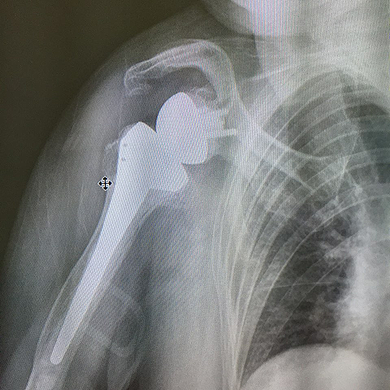

인공관절 치환술

회전근 개(어깨 힘줄) 광범위 파열의 봉합이 불가능한 경우에 수술적 치료로 역행성 견관절 전치환술이 필요 합니다.

역행성 전치환술은 대부분 회전근 개 파열성 관절증이나 골관절염이 생긴 경우에 시행 됩니다.

수술전 사진

수술후 사진